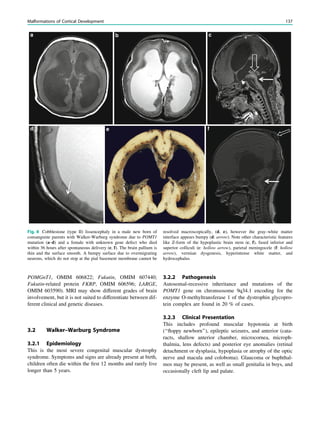

SPECT and PET WimVan Paesschen, Karolien Goffin and Koen Van Laere Contents 1 Introduction.......................................................................... 63 2 Ictal Onset Zone, Propagation Pathways, and Functional Deficit Zone............................................... 64 2.1 Ictal SPECT........................................................................... 64 2.2 2-[18 F]Fluoro-2-deoxy-D-glucose PET.................................. 64 3 Coregistration of SPECT and PET with MRI ................ 64 4 Functional Nuclear Imaging in the Presurgical Evaluation of Refractory Focal Epilepsy ......................... 64 4.1 Mesial Temporal Lobe Epilepsy with Hippocampal Sclerosis ................................................................................. 64 4.2 Malformations of Cortical Development.............................. 66 4.3 Dual Pathology ...................................................................... 68 4.4 MRI-Negative Refractory Focal Epilepsy............................ 68 5 Conclusion ............................................................................ 70 References...................................................................................... 70 Abstract Ictal perfusion single photon emission computed tomog- raphy and positron emission tomography of brain metabolism are functional nuclear imaging modalities that are useful in the presurgical evaluation of patients with refractory focal epilepsy, and provide information on the ictal onset zone, seizure propagation pathways, and functional deficit zones. Combined with electro- physiological and coregistered MRI data, these tech- niques allow a noninvasive presurgical evaluation in a growing number of patients with refractory focal epilepsy, and are particularly useful in patients with normal MRI findings, focal dysplastic lesions, dual pathology and discordant seizure symptoms, and elec- trophysiology and morphological data. In addition, these techniques may provide crucial information in the planning of invasive electroencephalography studies. 1 Introduction Single photon emission computed tomography (SPECT) and positron emission tomography (PET) are functional nuclear imaging modalities. SPECT allows the study of cerebral perfusion during the ictal and interictal states (Kapucu et al. 2009), and PET allows the study of cerebral metabolic and neurochemical processes. In the epilepsy clinic, 2-[18 F]fluoro-2-deoxy-D-glucose PET (FDG-PET) is commonly used to assess interictal and rarely ictal cerebral metabolism. Functional nuclear imaging is most useful in the presurgical evaluation of patients with refractory focal epilepsy, and can delineate the ictal onset, seizure propagation, and functional deficit zones (Rosenow and Lüders 2001). ‘‘Functional’’ means that the imaging results are critically dependent on the timing of tracer injection, i.e., ictal, postictal, or interictal, and the seizure type (Van Paesschen et al. 2007a; Goffin et al. 2008). For ictal W. Van Paesschen (&) Department of Neurology, University Hospital Leuven, Herestraat 49, 3000 Leuven, Belgium e-mail: wim.vanpaesschen@uzleuven.be K. Goffin Á K. Van Laere Division of Nuclear Medicine, University Hospital Leuven and Katholieke Universiteit Leuven, Leuven, Belgium H. Urbach (ed.), MRI in Epilepsy, Medical Radiology. Diagnostic Imaging, DOI: 10.1007/174_2012_561, Ó Springer-Verlag Berlin Heidelberg 2013 63

• 68.

SPECT interpretation, itis, therefore, important to be aware of the seizure types, the timing of the injection, ictal symptoms, and electroencephalography (EEG) data. Both FDG-PET and ictal SPECT can predict seizure-free out- come after epilepsy surgery (Knowlton et al. 2008). Ictal SPECT is probably the most sensitive imaging modality to delineate the ictal onset zone in extratemporal lobe epilepsy (Knowlton et al. 2008; Kim et al. 2009). 2 Ictal Onset Zone, Propagation Pathways, and Functional Deficit Zone Focal seizures start in the ictal onset zone, and can propa- gate through the brain (Rosenow and Lüders 2001). The functional deficit zone is the part of the cortex with an abnormal function between seizures, due to morphological or functional factors, or both. Understanding these concepts is crucial for proper interpretation of functional nuclear images. 2.1 Ictal SPECT In the absence of seizure propagation, the largest hyper- perfusion cluster with the highest z score represents the ictal onset zone. This pattern is usually observed with early ictal injections during simple or complex focal seizures, or in brain regions where ictal propagation is slow, and allows a reliable localization of the ictal onset zone on blinded assessment without prior knowledge of other data from the presurgical evaluation (Dupont et al. 2006). Often, ictal SPECT shows propagated ictal activity, which is due to the slow time resolution of ictal SPECT with respect to seizure propagation. The transit time of a perfusion tracer from an arm vein to cerebral arteries is around 30 s. In addition, there is often a delay between seizure onset and injection of the perfusion tracer. Further, only around 60% of the perfusion tracer is extracted by nerve cells on the first pass (the other 40% is extracted later), contributing to the slow time resolution of ictal SPECT. Propagation patterns can be seen in all focal epi- lepsies, but most often in frontal lobe epilepsy (Dupont et al. 2006). Ictal SPECT injections during secondary gen- eralized seizures show more areas of propagation than during focal seizures without generalization (Varghese et al. 2009). In the case of propagation, ictal hyperperfusion can be observed outside the ictal onset zone. The propagated activity may be represented by the largest hyperperfusion cluster with the highest z score, and is usually con- nected with the hyperperfusion cluster of the ictal onset zone though a small trail of hyperperfusion, which we have called an ‘‘hourglass pattern’’ (Dupont et al. 2006). Propagation may be towards another lobe, ipsilateral, or contralateral. A reliable blinded assessment of subtraction ictal SPECT coregistered with MRI (SISCOM) data without knowledge of the other data from the presurgical evaluation is often not possible. 2.2 2-[18 F]Fluoro-2-deoxy-D-glucose PET Hypometabolism on FDG-PET usually encompasses the ictal onset zone, but tends to be larger. There is evidence to suggest that both the ictal onset zone and seizure propaga- tion pathways become hypometabolic interictally, repre- senting the functional deficit zone (Rosenow and Lüders 2001; Van Paesschen et al. 2007a). The pattern of hypo- metabolism reflects the seizure types prior to PET scanning (Savic et al. 1997). The difference between the ictal onset zone and the functional deficit zone is most clearly dem- onstrated in the rare event of ictal FDG-PET scanning (Van Paesschen et al. 2007b). In these cases, the ictal onset zone is hypermetabolic and the functional deficit zone is hypo- metabolic (Fig. 1). 3 Coregistration of SPECT and PET with MRI The most common epileptic lesions causing refractory focal epilepsy include hippocampal sclerosis, malformations of cortical development, tumor, vascular malformations, and infarct/contusion (Li et al. 1995). Subtraction ictal SPECT is routinely coregistered with MRI (SISCOM) because it improves the clinical usefulness in localizing the ictal onset zone and is predictive of seizure outcome (O’Brien et al. 1998, 2000). FDG-PET/MRI coregistration improves the detection of small dysplastic lesions (Chassoux et al. 2010; Goffin et al. 2010; Salamon et al. 2008). 4 Functional Nuclear Imaging in the Presurgical Evaluation of Refractory Focal Epilepsy 4.1 Mesial Temporal Lobe Epilepsy with Hippocampal Sclerosis 4.1.1 Ictal SPECT Ictal SPECT during a complex focal seizure in mesial temporal lobe epilepsy with hippocampal sclerosis usually shows early ipsilateral neocortical temporal lobe hyperper- fusion, frontal lobe hypoperfusion (ipsilateral more than contralateral), contralateral cerebellar hypoperfusion, and later parietal lobe hypoperfusion (Van Paesschen et al. 64 W. Van Paesschen et al.

• 69.

2003; Blumenfeld etal. 2004) (Fig. 2). Ictal SPECT during simple focal seizures in mesial temporal lobe epilepsy with hippocampal sclerosis can show a small hyperperfusion cluster confined to the temporal lobe, or may reveal no hyperperfusion in around 40% of cases (Van Paesschen et al. 2000; Van Paesschen and Ictal 2004), probably because the hyperperfusion is below the spatial resolution of ictal SPECT, which is around 7 mm. Seizure propagation towards the ipsilateral basal ganglia together with hypo- perfusion of associative brain regions correlates with con- tralateral dystonic posturing of the arm (Kim et al. 2007; Chassagnon et al. 2009). Seizures can propagate to the contralateral temporal lobe, and when the ictal SPECT injection is given after seizure propagation, SISCOM may show hyperperfusion in the contralateral temporal lobe (Cho et al. 2010). Early ictal SPECT injection can obviate this problem of seizure propagation (Van Paesschen et al. 2000). Different propagation patterns in mesial temporal lobe epilepsy with hippocampal sclerosis are not of prog- nostic significance with respect to seizure outcome after epilepsy surgery (Kim et al. 2007). 4.1.2 2-[18 F]Fluoro-2-deoxy-D-glucose PET Interictal FDG-PET findings in mesial temporal lobe epi- lepsy with hippocampal sclerosis have been well described. Hypometabolism is present in the ipsilateral temporal lobe in around 95% of cases, but also in regions outside the ictal onset zone, including the contralateral temporal lobe in up to 40% of cases, the ipsilateral thalamus in around 65% of cases, ipsilateral basal ganglia in 45% of cases, the ipsi- lateral insula in 50% of cases, the ipsilateral basal frontal lobe in around 30% of cases, and the ipsilateral parietal lobe in up to 30% of cases (Henry et al. 1990, 1993) (Fig. 2). In mesial temporal lobe epilepsy with hippocampal sclerosis, the extent and severity of hypometabolism is not related to surgical outcome (Lee et al. 2002). Interictal ipsilateral frontal lobe hypometabolism in mesial temporal lobe epi- lepsy with hippocampal sclerosis tends to coincide with ictal SPECT hypoperfusion, which could represent surround inhibition (Nelissen et al. 2006). Frontal lobe hypometab- olism in mesial temporal lobe epilepsy with hippocampal sclerosis could explain frontal lobe cognitive deficits (Takaya et al. 2006; Jokeit et al. 1997). Fig. 1 2-[18 F]Fluoro-2-deoxy-D-glucose positron emission tomogra- phy (PET) in Rasmussen encephalitis. a Three-dimensional stereotac- tic surface projection analysis of ictal PET. The patient was a 26-year-old woman with Rasmussen encephalitis affecting the right cerebral hemisphere, with left-sided focal motor status epilepticus. Ictal PET was performed because electroencephalography did not allow lateralization, and showed hypermetabolism in the right hemisphere, consistent with status epilepticus. The left hemisphere was severely hypometabolic. b Stereotactic surface projection analysis of interictal PET images 1 year after a right functional hemispherot- omy, which rendered her seizure-free. The right hemisphere became hypometabolic. The structurally normal left hemisphere became normometabolic, which was accompanied by important cognitive improvements, consistent with a recovery of the functional deficit zone SPECT and PET 65

• 70.

4.2 Malformations ofCortical Development Malformations of cortical development represent a spec- trum of congenital structural abnormalities of cerebral cortical development, which are a major cause of refractory focal epilepsy (Barkovich et al. 2005; Palmini et al. 2004). Malformations due to abnormal proliferation (Barkovic class I), including cortical hamartomas, cortical dysplasia with balloon cells, dysembryoplastic neuroepithelial tumors, gangliogliomas, and gangliocytomas, have a better outcome than malformation due to abnormal proliferation (Barkovic class II) and malformations due to abnormal cortical organization (Barkovic class III) (Chang et al. 2011). Focal cortical dysplasia, characterized by abnormal neuroglial proliferation, is the most frequent malformation of cortical development in patients referred for presurgical evaluation (Lüders and Schuele 2006). Focal cortical dys- plasia can be classified into three types (Blümcke et al. 2011). Complete resection of electrocorticographic and structural abnormalities appears to be most predictive of long-term seizure outcome (Chang et al. 2011). Functional nuclear imaging is a useful technique in the presurgical evaluation of refractory focal epilepsy due to malformations of cortical development. 4.2.1 Ictal SPECT Malformations of cortical development are intrinsic epilep- togenic lesions, since the ictal onset zone is within the dys- plastic cortex. Dysplastic cortex may not always be visible on MRI and, therefore, the ictal onset zone may be at the border of an MRI-visible dysplastic lesion (Blümcke et al. 2011; Marusic et al. 2002). Ictal SPECT is particularly useful to delineate the ictal onset zone in focal dysplastic lesions, even when these are not visible on MRI (Van Paesschen et al. 2007a; Dupont et al. 2006; Kim et al. 2011). O’Brien et al. (2004) reported that a model combining SISCOM concor- dance with the surgical resection site and the extent of MRI lesion resection was predictive of postoperative seizure Fig. 2 Ictal single photon emission computed tomography (SPECT) and FDG-PET in mesial temporal lobe epilepsy with hippocampal sclerosis. The patient was a 55-year-old woman with mesial temporal lobe epilepsy associated with left hippocampal sclerosis. a Subtraction ictal SPECT coregistered with MRI (SISCOM) of a complex focal seizure which lasted 73 s, with initiation of ictal SPECT tracer injection 38 s after seizure onset. The largest hyperperfusion cluster (yellow–red) with the highest z score was in the left superior and middle temporal gyrus, and was connected with a small trail of hyperperfusion (white arrow) coming from the left hippocampal sclerosis, i.e., the largest hyperperfusion cluster probably represented propagated seizure activity. Areas of hypoperfusion (blue) visible on this image were the contralateral temporal lobe and frontal lobe at the midline. b Three-dimensional stereotactic surface projection analysis of FDG-PET images showed left temporal lobe hypometabolism (white arrow) 66 W. Van Paesschen et al.

• 71.

outcome. In refractoryfocal epilepsy due to a single MRI- visible focal dysplastic lesion, we found that overlap between the SISCOM hyperperfusion cluster and the MRI-visible focal dysplastic lesion in a noninvasive presurgical evalua- tion with concordant data may suffice to proceed to epilepsy surgery aimed at removing the MRI-visible focal dysplastic lesion and the part of the hyperperfusion cluster within and immediately surrounding the focal dysplastic lesion (Dupont et al. 2006) (Fig. 3). 4.2.2 2-[18 F]Fluoro-2-deoxy-D-glucose PET Focal cortical dysplasia shows a focal or regional area of hypometabolism on FDG-PET in around 65–80% of cases (Chassoux et al. 2010; Goffin et al. 2010; Salamon et al. 2008; Kim et al. 2011). FDG-PET/MRI coregistration and partial volume correction improves detection of cortical dysplasia (Chassoux et al. 2010; Goffin et al. 2010; Salamon et al. 2008). FDG-PET is especially useful to detect the milder Palmini type I lesions, which may not be visible on Fig. 3 Multimodality imaging in the presurgical evaluation of refractory focal epilepsy. The patient was a 14-year-old boy with refractory frontal lobe epilepsy with focal motor seizures in his left limbs. a Fluid- attenuated inversion recovery (FLAIR) showed a focal cortical dysplasia that was visible as an area of slightly hyperintense and thickened cortex, located on the medial border of the right superior frontal gyrus (white cross). b Multimodal imaging including magnetization- prepared rapid gradient echo, subtracted ictal SPECT (red), and motor functional MRI of the foot (yellow), hand (green), and corticospinal tract (blue), coregistered with FLAIR (a). The SISCOM hyperperfusion cluster overlapped with the focal cortical dysplasia, which provided an excellent delineation of the epileptogenic zone, i.e., the region that the neurosurgeon has to remove to render the patient seizure-free. However, motor functional MRI of the foot confirmed that the epileptic lesion was within eloquent cortex. Surgery has not been offered SPECT and PET 67